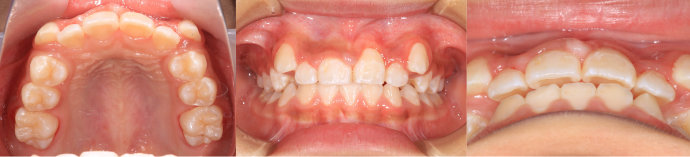

| Case3 |

| 受け口 |

| <治療前> |

| <治療後> |

| 主訴 |

上の歯がねじれている |

| 診断名 |

叢生を伴う反対咬合 |

| 年齢 |

10歳 |

| 使用装置 |

マルチブラケット装置 |

| 抜歯部位 |

永久歯の抜歯は無し |

| 治療期間 |

3年6か月 |

| 治療費概算 |

検査・診断料:5万円+税 装置・技術料:25万円+税 おおよそ1か月ごとの処置・管理料:5,000円+税 保定装置料:5万円+税 |

| リスク・副作用 |

う蝕 |